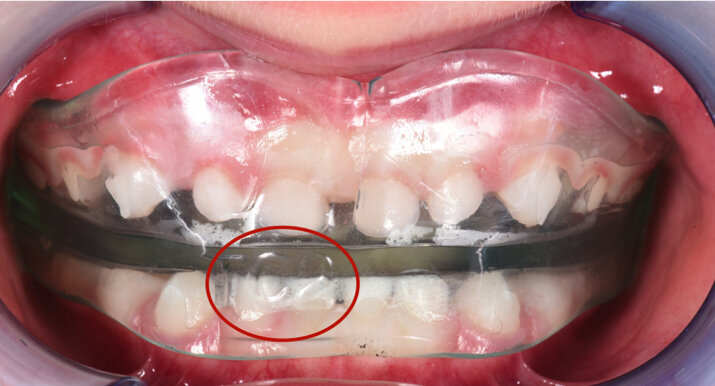

Analisi dei dispositivi funzionali Elastodontici Il trattamento con il Bio-Attivatore A.M.C.O.P. by Micerium è sorprendentemente semplice, naturale, innovativo e non invasivo e può essere considerato una straordinaria bio-ortopedia oro-cranio-facciale. È infatti un dispositivo ortodontico elastico di grande validità terapeutica di carattere funzionale, specificatamente ortopedico del sistema dento-cranio-facciale.

È un armonizzatore delle distorsioni simultanee delle basi scheletriche mascellari e mandibolari ed è adatto per il livellamento dei piani occlusali inclinati, ruotati e torsionati per una corretta funzione ed un buon equilibrio della bocca. Il dispositivo è anche un validissimo strumento di lavoro decontratturante, detensionale di diverse problematiche muscolo-tensive e si rivela molto indicato anche per la riabilitazione delle articolazioni temporo-mandibolari (ATM). Se correttamente utilizzato, è in grado di procurare processi antinfiammatori e riparativi determinanti che vanno al di là di semplici trattamenti occlusali che danno al paziente l’opportunità di rimediare scompensi di carattere sintomatico e quindi psicologico.

I Bio-Attivatori A.M.C.O.P. by Micerium costituiscono la sintesi di tutti gli attivatori funzionali esistenti e sono adatti ad una riabilitazione funzionale e personalizzata del paziente. Essi forniscono una visione più ampia e corretta del trattamento, poiché il dispositivo agisce come crescita armoniosa del sistema dentocranio-facciale e ne stabilizza il risultato ottenuto. La forma nasce per necessità del nostro corpo di espletare una funzione. Il dispositivo è indicato per migliorare le funzioni neurovegetative della bocca, della deglutizione, della masticazione, della fonazione e della respirazione per migliorare la funzione naso-ventilatoria con un ritorno alla normofunzione del distretto naso-oro-laringo-faringeo.

Gli apparecchi elastodontici sono realizzati con un materiale termoplastico in grado di interagire in maniera attiva con l’occlusione, i muscoli della lingua, il muscolo orbicolare ma nello stesso tempo sono in grado di creare un spazio cosiddetto elastodontico il quale rappresenta lo spazio ideale tra la muscolatura della lingua (forza centrifuga) e quelle delle labbra (forza centripeta) all’interno del quale avviene lo spostamento degli elementi dentali; quindi non è l’apparecchio stesso a determinare il movimento dentale ma è l’equilibrio che si instaura tra la muscolatura delle labbra e quella della lingua a creare uno spazio neutro all’interno del quale si posizionano gli elementi dentali stessi.

I dispositivi elastodontici possono essere standard oppure individualizzati, ossia realizzati direttamente sul modello delle arcate del paziente e proprio questi ultimi costituiscono un importantissimo strumento nelle mani dell’ortodontista per la correzione delle malocclusioni più gravi anche nei pazienti adulti. Questi dispositivi hanno alla base il meccanismo di funzionamento degli attivatori di Soulet e Besombes nati negli anni ‘50 dall’idea di due ortodontisti, il professor Soulet ed il professor Besombes. Studiati per essere utilizzati come apparecchi di contenzione, questi si rivelarono dei preziosi dispositivi ortopedici. Questi attivatori sono formati da uno scudo vestibolare e da una uno linguale in materiale termoplastico che lascia un’area centrale libera nella quale avviene lo spostamento biologico degli elementi dentali: lo spazio elastodontico. Questi apparecchi hanno, quindi, la capacità di simulare i rapporti corretti di arcate modificate e corrette in I classe ed indurranno così, per differenti spessori dell’elastodontico, effetti propulsivi, retropulsivi od espansivi.

Il meccanismo di funzionamento dei dispositivi elastodontici è tale per cui attraverso l’elasticità più o meno elevata del materiale è possibile intervenire in maniera tridimensionale all’interno di una realtà anch’essa tridimensionale qual è la cavità orale; a differenza dei comuni dispostivi funzionali standard in grado di lavorare bidimensionalmente a causa di un rapporto occlusale spesso alterato dalla presenza di placche o docce che rendono la terapia meno biologica impedendo il raggiungimento dell’ intercuspidazione durante la terapia stessa.

Caso 2 Paziente di anni 4, malocclusione dentale di III Classe, morso crociato monolaterale dx. La paziente viene trattata con dispositivo Amcop TC 2, il quale indossato tutte le notti e 1 ora di pomeriggio in 8 mesi risolve la malocclusione ripristinando il corretto rapporto occlusale; durante la terapia si riscontra un netto miglioramento della respirazione nasale e quindi il ripristino delle normali funzioni respiratorie. Il dispositivo, nei mesi successivi, viene indossato dalla paziente solo la notte per stabilizzare il caso e per guidare la crescita nel miglior modo possibile; all’età di 6 anni la paziente viene sottoposta a check-up ortodontico completo e quindi a panoramica e teleradiografia per poter analizzare anche la previsione di crescita e stabilire un eventuale step elastodontico (Figg. 15-23).

Fig. 17

Fig. 18